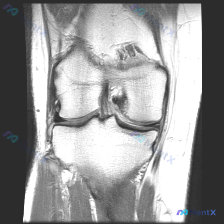

单张膝关节冠状位MRI读片,你能抓住所有异常吗?

刚梳理完一份膝关节MRI读片病例,核心问题是「这张图像中可视觉识别的潜在异常是什么?」,标准答案提示是软骨异常,不过整理完发现这个病例其实挺值得讨论,分享一下完整分析思路。

这是一张膝关节MRI冠状位影像,我们先整理客观观察到的所有征象:

- 骨骼结构:股骨远端、胫骨平台骨皮质连续,没有明显骨折移位,但股骨内侧髁承重面、胫骨平台内侧可见局部骨信号异常

- 关节间隙:内侧关节间隙比外侧明显变窄,这是典型的退变性改变征象

- 软骨与半月板:内侧间室是重点,内侧半月板体部形态异常、信号增高,和关节面的关系发生改变;外侧半月板形态信号都基本正常

- 韧带肌腱:内侧副韧带走行连续,外侧副韧带区域没有明显异常

- 软组织:关节腔内没有明显积液征象

异常信号集中在内侧间室:内侧半月板信号增高、形态不规整,提示退变或撕裂;股骨内侧髁软骨下骨可见斑片状异常信号,结合间隙狭窄提示软骨下骨重塑硬化或退行性骨髓水肿,所有病变边界偏模糊,符合慢性改变特点。